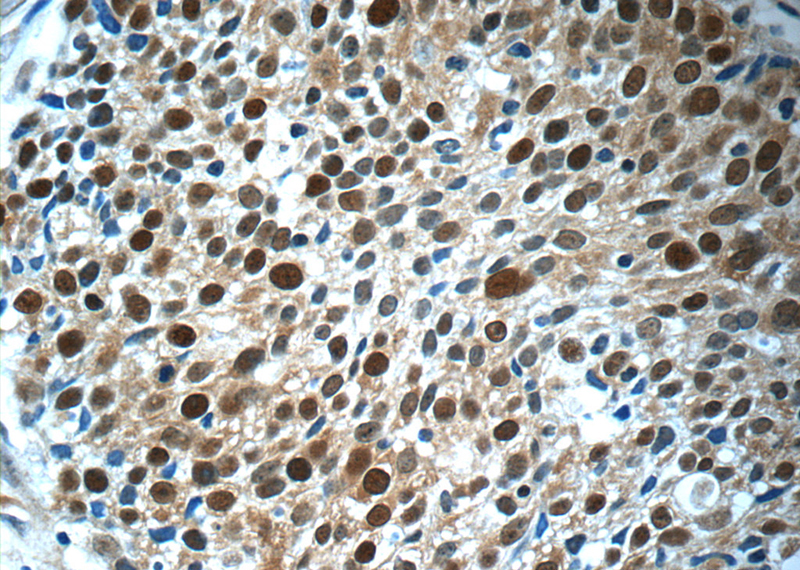

Immunohistochemistry of paraffin-embedded human lung cancer tissue slide using Catalog No:112557(MCM7 Antibody) at dilution of 1:50 (under 40x lens)